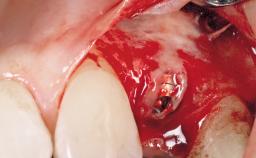

Late Flapless Placement of an Implant in a Maxillary Left Central Incisor Site

A 39-year-old male patient presented with a chief complaint of discomfort and gingival discoloration around his maxillary left central incisor. He was in good general health and was a non-smoker. His past dental history was significant because of the traumatic fracture of tooth 21 in a sporting accident at age 13. Initial dental treatment included endodontic therapy and a full-coverage restoration. The patient became symptomatic 5 years later, when structural failure of the tooth resulted in the dislodgment of the crown. Endodontic retreatment, apical surgery, and post-and-core restoration were performed.

| Bone Augmentation | Horizontal|Staged |

| Augmentation Materials | Xenogenous|Membrane |

| Soft Tissue Grafting | Simultaneous |